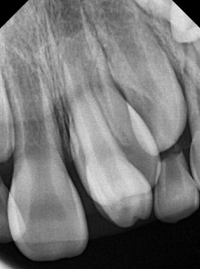

과잉치의 존재는 주변 치아의 정상적인 발육을 방해할 수 있으며, 경우에 따라서는 통증을 유발하거나 치아 배열의 이상을 초래할 수 있습니다. 진단은 주로 치과 엑스레이를 통해 이루어지며, 치료는 과잉치의 위치와 환자의 상태에 따라 다릅니다. 일반적으로는 외과적 발치가 필요할 수 있으며, 이후에는 교정 치료를 통해 정상적인 치열을 유지합니다.

1) 영구치 맹출을 막는 경우

2) 영구치 뿌리를 흡수시키는 경우

과잉치를 잇몸 절개 수술을 해서라도 뽑아야 하는 경우는 결국 영구치에 영향을 주냐, 안주냐에 따라 결정됩니다. 만약 과잉치로 인해 영구치가 못 나오는 경우는 수술을 통해서라도 제거를 해주셔야 합니다. 또는 과잉치로 인해 영구치 뿌리가 흡수되는 경우(드물긴 합니다) 또한 영구치에 위해를 가하기 때문에 제거해주셔야 합니다. 과잉치가 뼈 안쪽에 있다가 간혹 물주머니 (물혹)를 만드는 경우가 있습니다. 이 경우도 제거를 해주셔야 물혹이 더 커지지 않습니다.